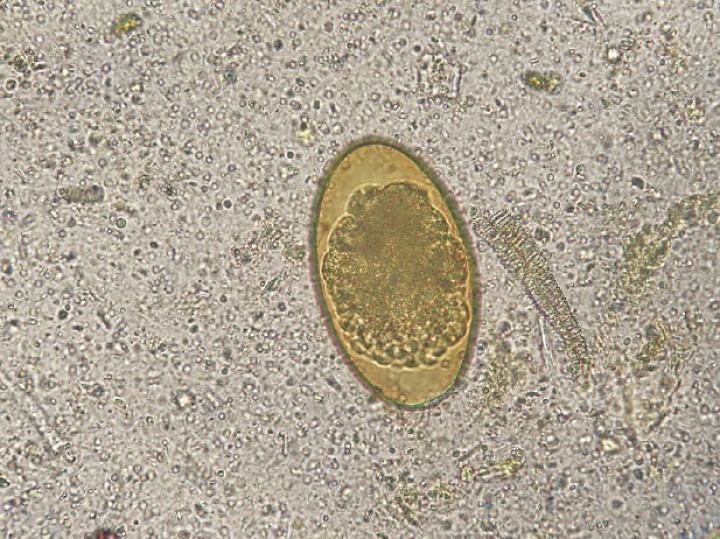

Se encontraron huevos de oxiúridos (Fig. 9) en las cuatro especies de tortugas, pero la ausencia de caracteres diferenciales no permite identificar la especie a la que pertenecen. No obstante, en algunos individuos de T. graeca se encontraron también algunas larvas y adultos expulsados de forma espontánea, que han podido ser identificados como Tachigonetria sp. Respecto a los ascáridos, solo se han encontrado en T. graeca y T. hermanni. Las características de los huevos no permiten una identificación más específica (Fig. 10), pero los adultos expulsados de forma espontánea en algunos individuos de T. graeca han sido identificados como Angusticaecum holopterum.

<p>Imagen de huevo de oxiúrido (Lugol, 40 x).</p>

Figura 9

Imagen de huevo de oxiúrido (Lugol, 40 x).

<p>Imagen de huevo de ascárido (Lugol, 100 x).</p>

Figura 10

Imagen de huevo de ascárido (Lugol, 100 x).

Respecto a los nematodos, en la mayoría de las muestras la identificación se realizó por la morfología de los huevos, que presentan características similares en las distintas especies de cada grupo y es relativamente fácil identificar si pertenecen a oxiúridos o a ascáridos. Los de los oxiúridos suelen ser elipsoides aplanados unilateralmente (asimétricos)[ Bouamer S, Morand S, Bourgat R. Redescription of Mehdiella microstoma and description of Mehdiella petterae sp. N., with a new definition of the genus Mehdiella Seurat, 1918 (Nematoda: Pharyngodonidae). Folia Parasitol, 2001a; 48: 132-138. [PubMed] , Bouamer S, Morand S, Bourgat R. Oxyuroids of Palearctic Testudinidae – new definition for Alaeruis Saeurat, 1918 (Nematoda: Pharyngodonidae) and redescription of Alaeuris numidica (Seurat, 1918). J Parasitol, 2001b; 87: 128-133. [PubMed] , Bouamer S, Morand S, Kara M. Redescription of four species of Mehdiella from Testudinidae, with a key to the species and discussion on the relationships among the species of this genus. Parasite, 2003; 10: 333-342. [PubMed] , Mehlhorn H, Düwel D, Raether W. Parásitos de reptiles y anfibios en: Atlas de Parasitología Veterinaria. Grass ediciones. Barcelona, 1992; 394- 406. ] (Fig. 9) y los de los ascáridos, esféricos u ovoides y de cáscara gruesa[ Bouamer S, Morand S, Bourgat R. Redescription of Mehdiella microstoma and description of Mehdiella petterae sp. N., with a new definition of the genus Mehdiella Seurat, 1918 (Nematoda: Pharyngodonidae). Folia Parasitol, 2001a; 48: 132-138. [PubMed] , Bouamer S, Morand S, Bourgat R. Oxyuroids of Palearctic Testudinidae – new definition for Alaeruis Saeurat, 1918 (Nematoda: Pharyngodonidae) and redescription of Alaeuris numidica (Seurat, 1918). J Parasitol, 2001b; 87: 128-133. [PubMed] , Bouamer S, Morand S, Kara M. Redescription of four species of Mehdiella from Testudinidae, with a key to the species and discussion on the relationships among the species of this genus. Parasite, 2003; 10: 333-342. [PubMed] , Mehlhorn H, Düwel D, Raether W. Parásitos de reptiles y anfibios en: Atlas de Parasitología Veterinaria. Grass ediciones. Barcelona, 1992; 394- 406. ] (Fig. 10). La alta prevalencia encontrada en nuestro estudio para los oxiúridos (71,4 % global) coincide con otros estudios realizados.[ Panini R, Menettii C, Mancianti F. Coprological survey in pet reptiles in Italy. Vet Rec, 2011; 169, 207. [PubMed] , Pasmans F, Blahak S, Martel A, Pantchev N. Introducing reptiles into a captive collection: The role of the veterinarian. Vet J, 2008; 175, 53–68. [PubMed] , Traversa D, Capelli G, Iorio R, et al. Epidemiology and biology of nematofauna affecting Testudo hermanni, Testudo graeca and Testudo marginata in Italy. J Parasitol Res, 2005; 98: 14–20. , Rataj AV, Lindtner-Knific R, Vlahovic K, Mavri U, Dovc A. Parasites in pet reptiles. Acta Vet Scand, 2011; 53, 33. [PMC] , Hedley K, Eatwell D, Shaw J. Gastrointestinal parasitic burdens in UK tortoises: a survey of tortoise owners and potential risk factors. Vet Rec, 2013; 173: 525. [PubMed] , McGuire JL, Miller EA, Norton TM, et al. Intestinal parasites of the gopher tortoise (Gopherus Polyphemus) from eight populations in Georgia. J Parasitol Res, 2013; 112: 4205-4210. [PubMed] ] Asimismo, el porcentaje de infestaciones concomitantes con oxiúridos y ascáridos, que asciende a un 44,64 % (50/112) (Tabla 1), es considerable, lo cual es relativamente común.[ Schneller P, Pantchev N. Parasitology in Snakes, Lizards and Chelonians. Ed Chimaira, Frankfurt am Main, 2008: 90- 172. ]